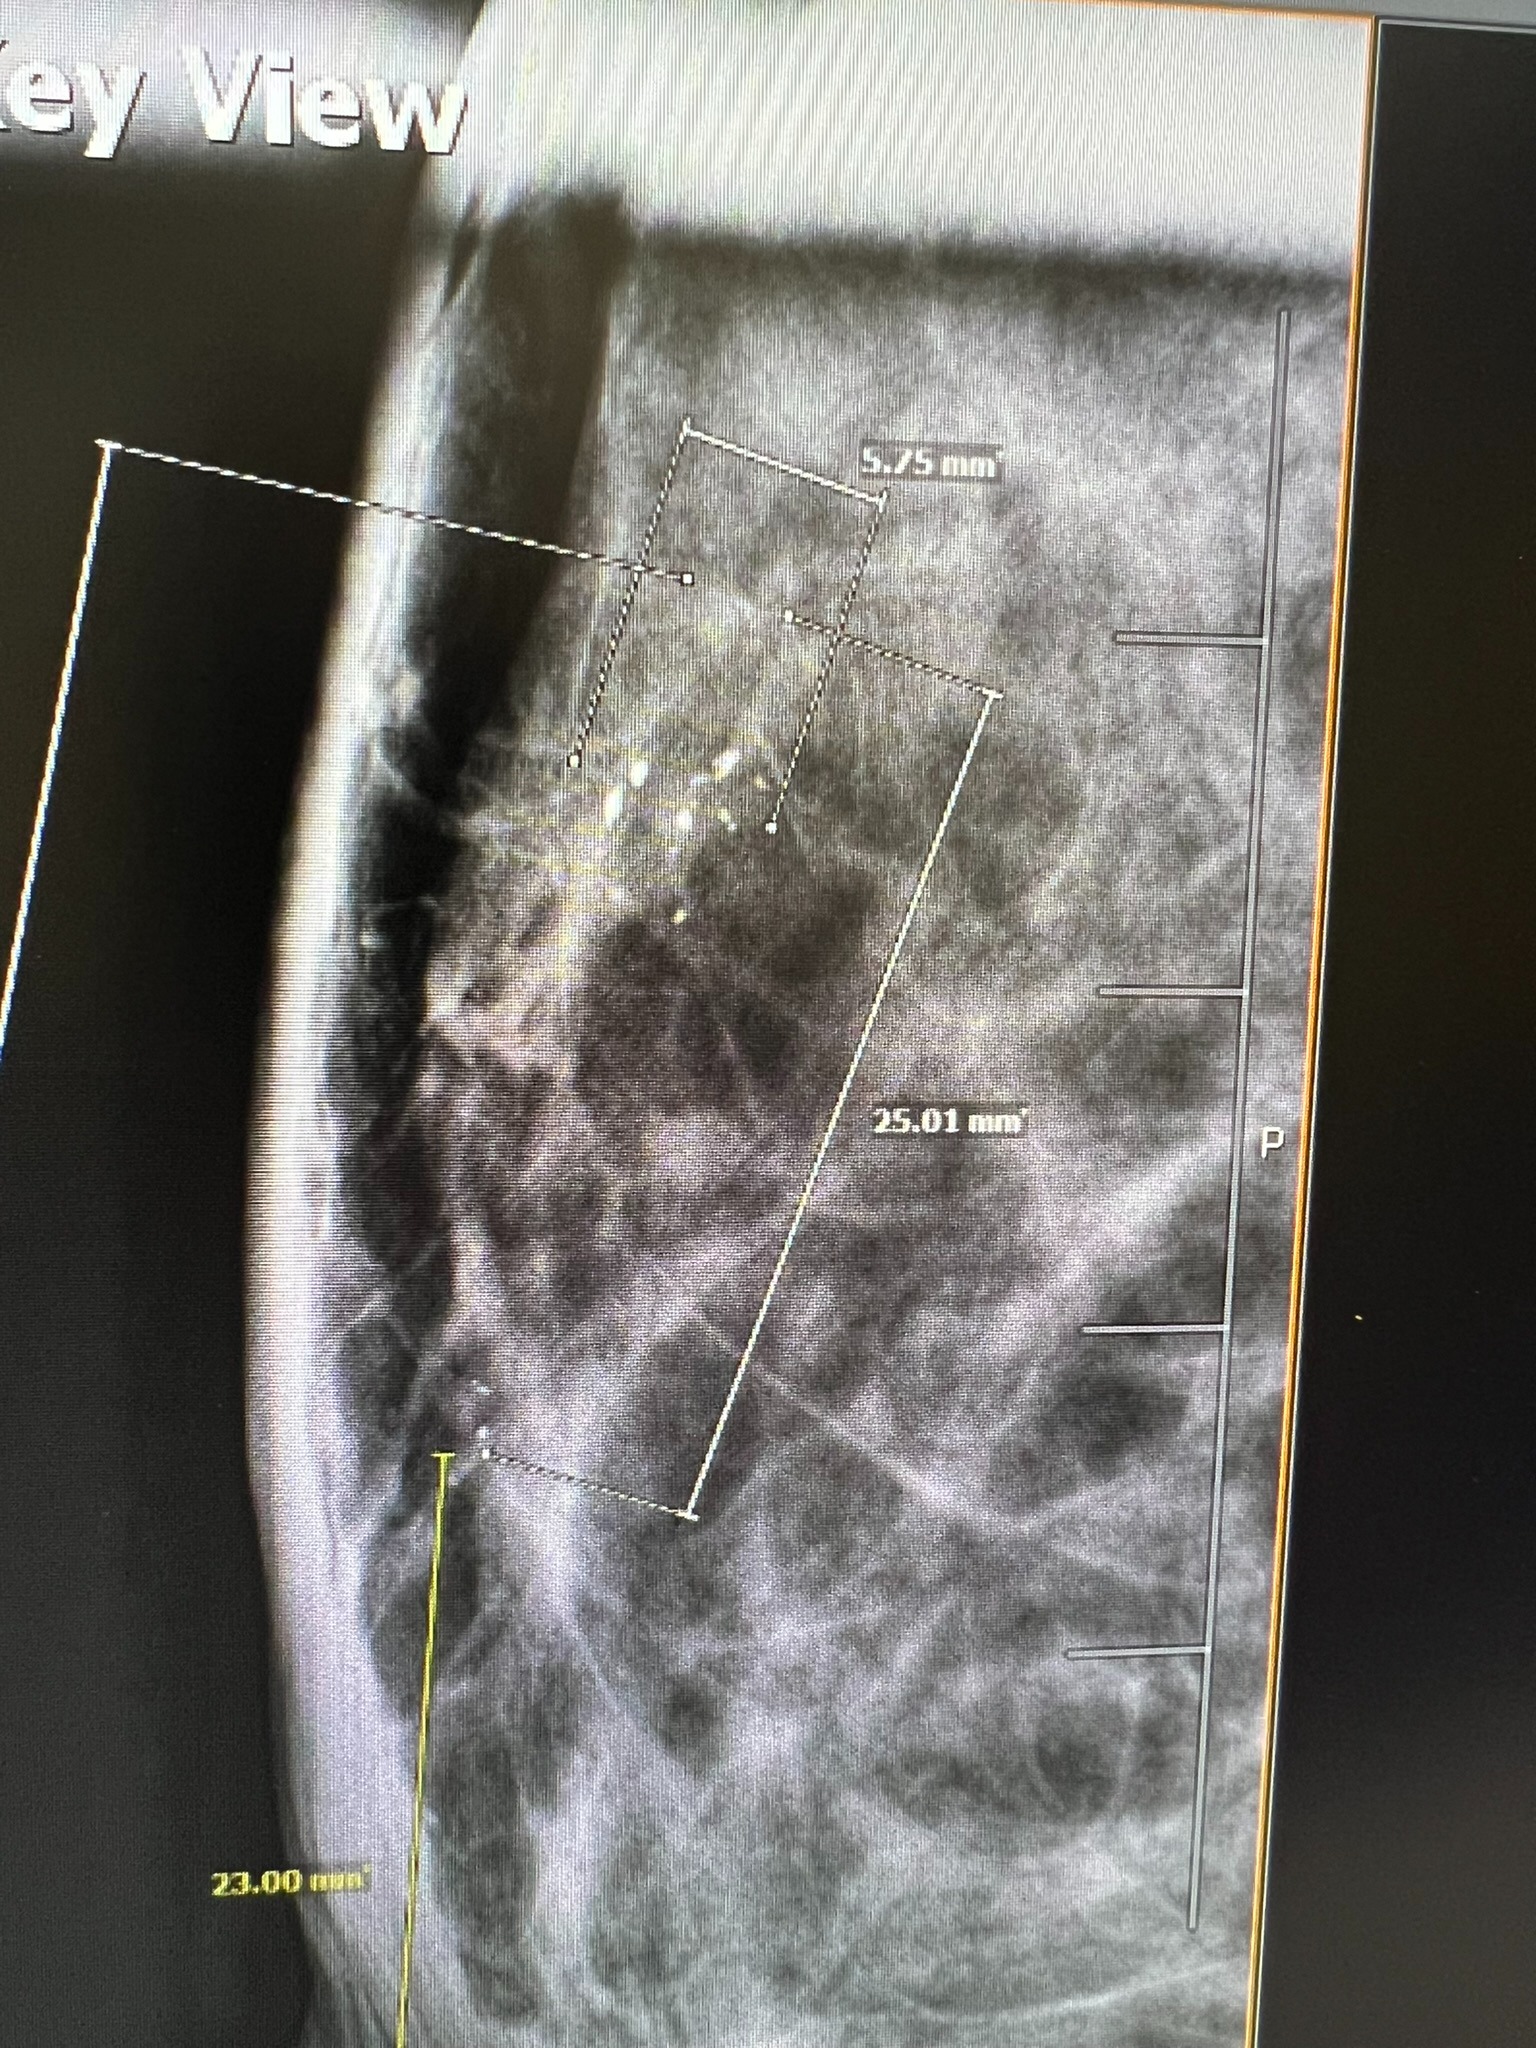

In late May 2025, after an insurance change, I scheduled a routine mammogram and was able to get one the same day. Two days later, I was notified of abnormal results. After a diagnostic mammogram and biopsy, I was diagnosed with DCIS—Stage 0 breast cancer, grade 2. An MRI later confirmed the diagnosis and showed a broader area of concern. This all happened just weeks before I competed at APO Nationals in powerlifting, which I went on to complete before beginning the next phase of appointments and planning. Because I qualified for APO Worlds, my oncologist and I agreed it was reasonable to delay a double mastectomy until after November while managing the cancer with medication. Training and competing during treatment was extremely difficult, but I did it.